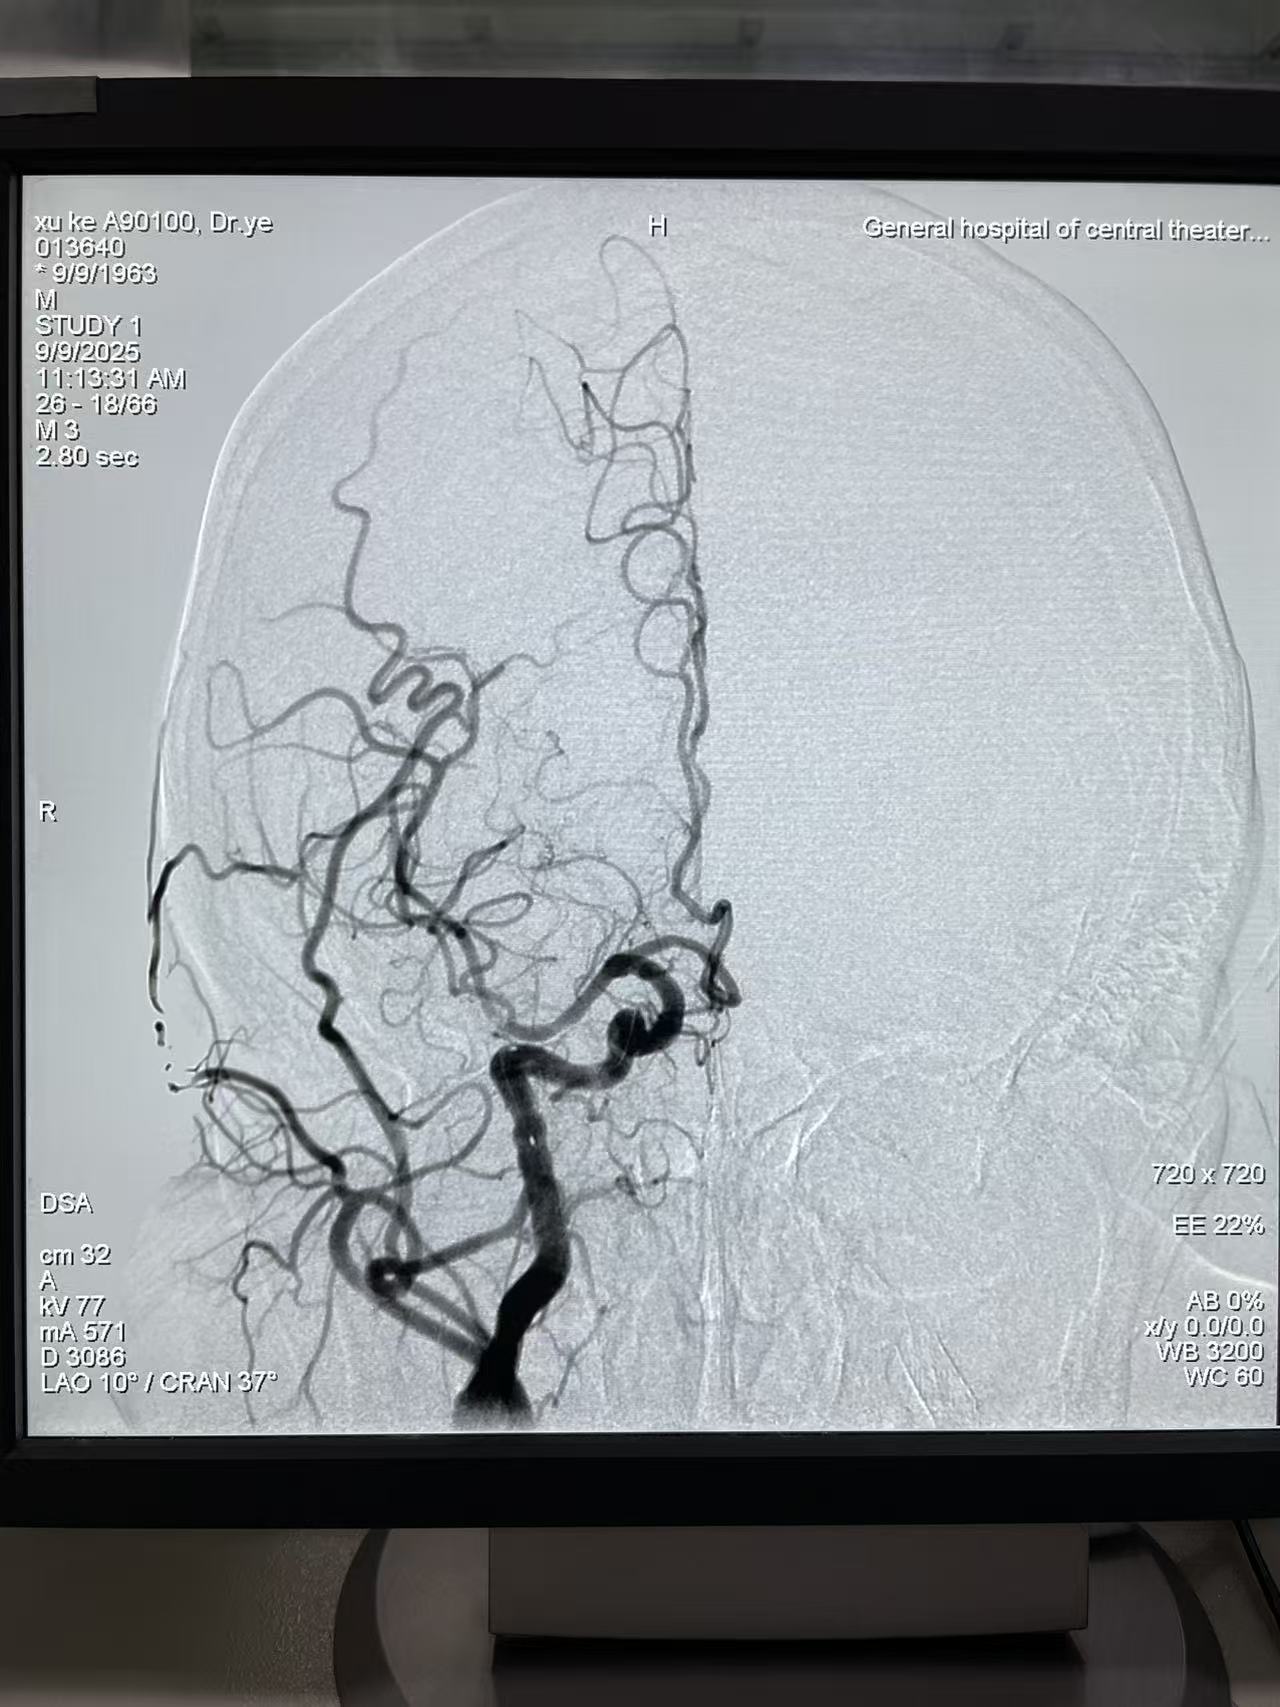

他的技术突破极具标志性——曾独立完成国际首例“冠脉+颅内血管并联狭窄(前循环大脑中动脉+后循环椎动脉)一站式介入手术”,带领团队完成百余例泛血管疾病综合介入治疗,充分展现了跨系统血管诊疗的整合能力。此外,他在选择性心脑血管造影、血管封堵术等基础介入技术上经验深厚,年均主刀手术超600例,累计收治患者超9万人次。